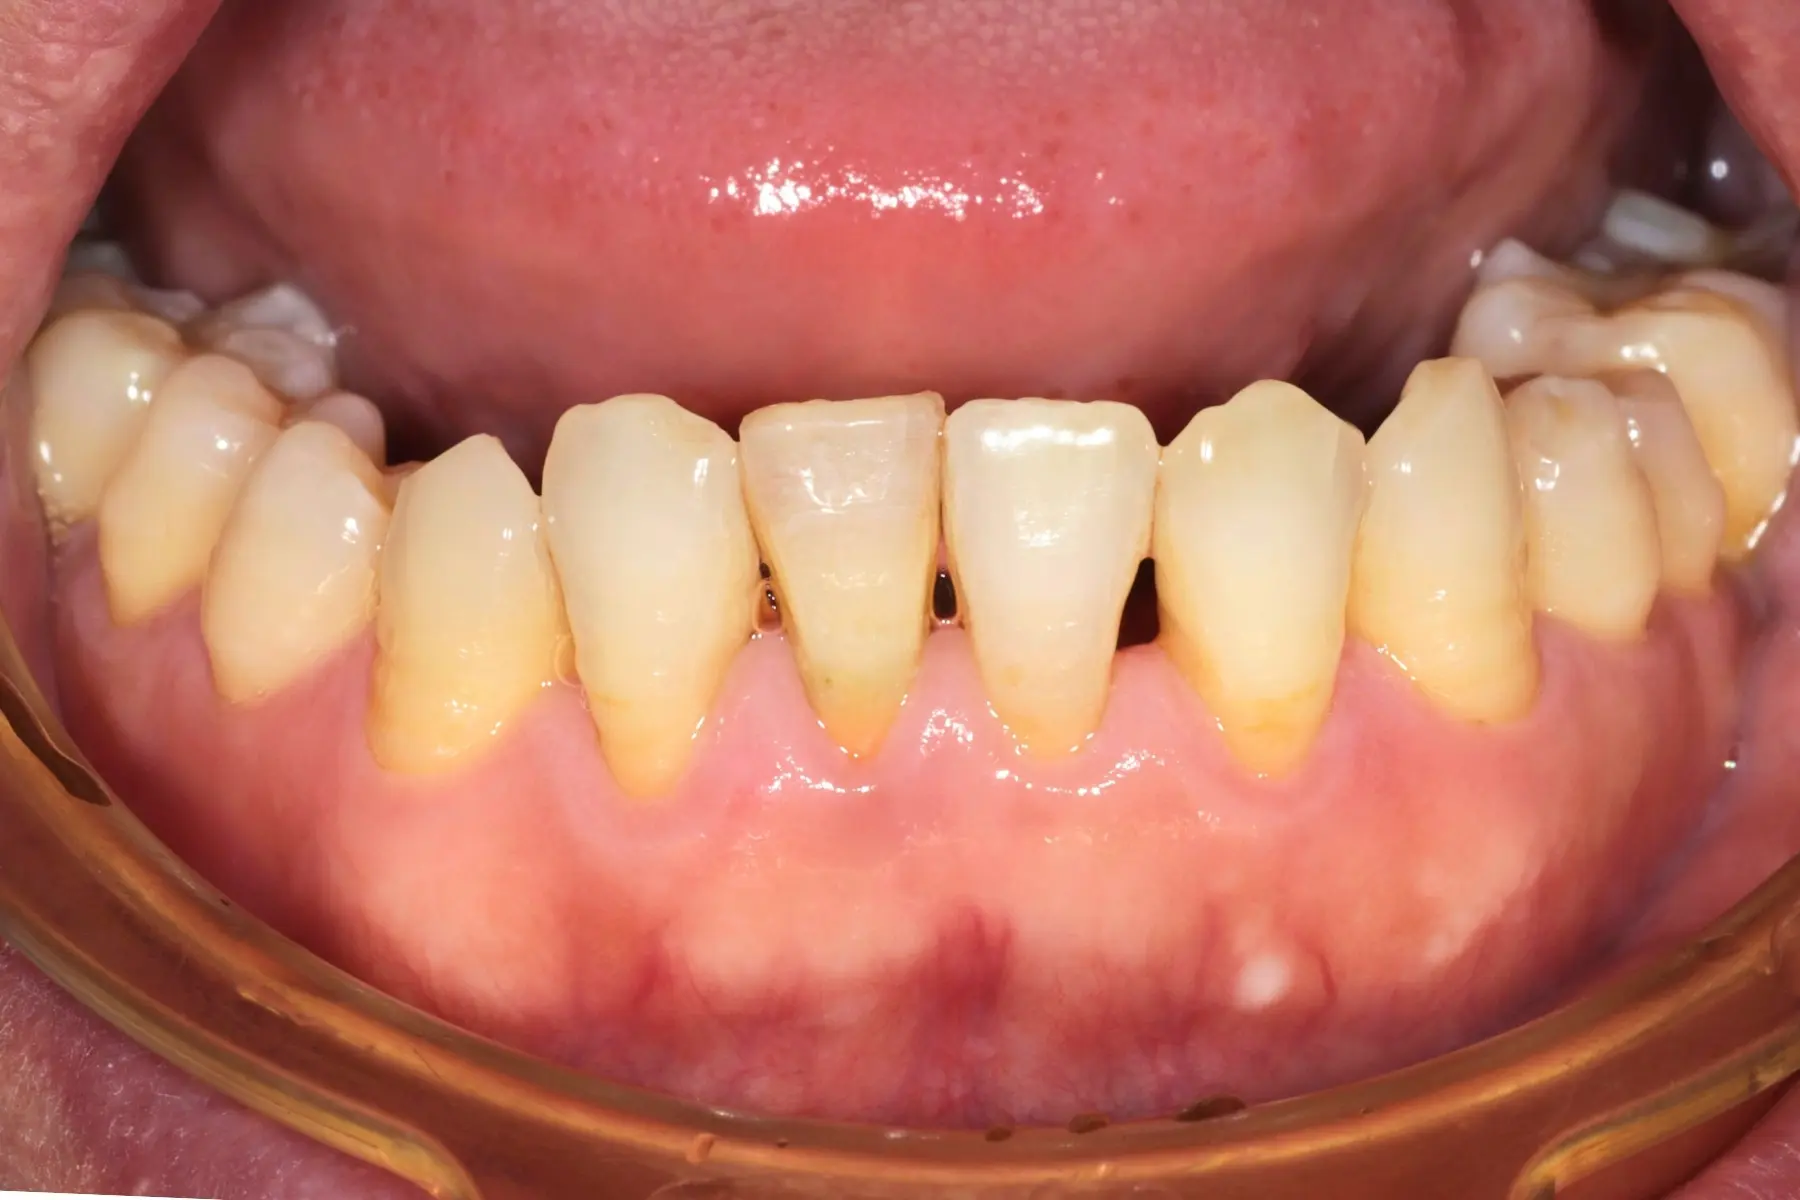

牙齦紅腫出血、牙縫容易塞食物

• 術前 42

術後 40

牙周治療

主治醫師

• 鍾國耀

治療時間

三次療程

主訴

右上前牙牙齦反覆腫脹化膿